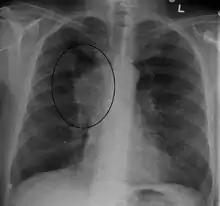

The main techniques of diagnosing SVCS are with chest X-rays (CXR), CT scans, transbronchial needle aspiration at bronchoscopy and mediastinoscopy.[5] CXRs often provide the ability to show mediastinal widening and may show the presenting primary cause of SVCS.[5] However, 16% of people with SVC syndrome have a normal chest X-ray. CT scans should be contrast enhanced and be taken on the neck, chest, lower abdomen, and pelvis.[5] They may also show the underlying cause and the extent to which the disease has progressed.[5]